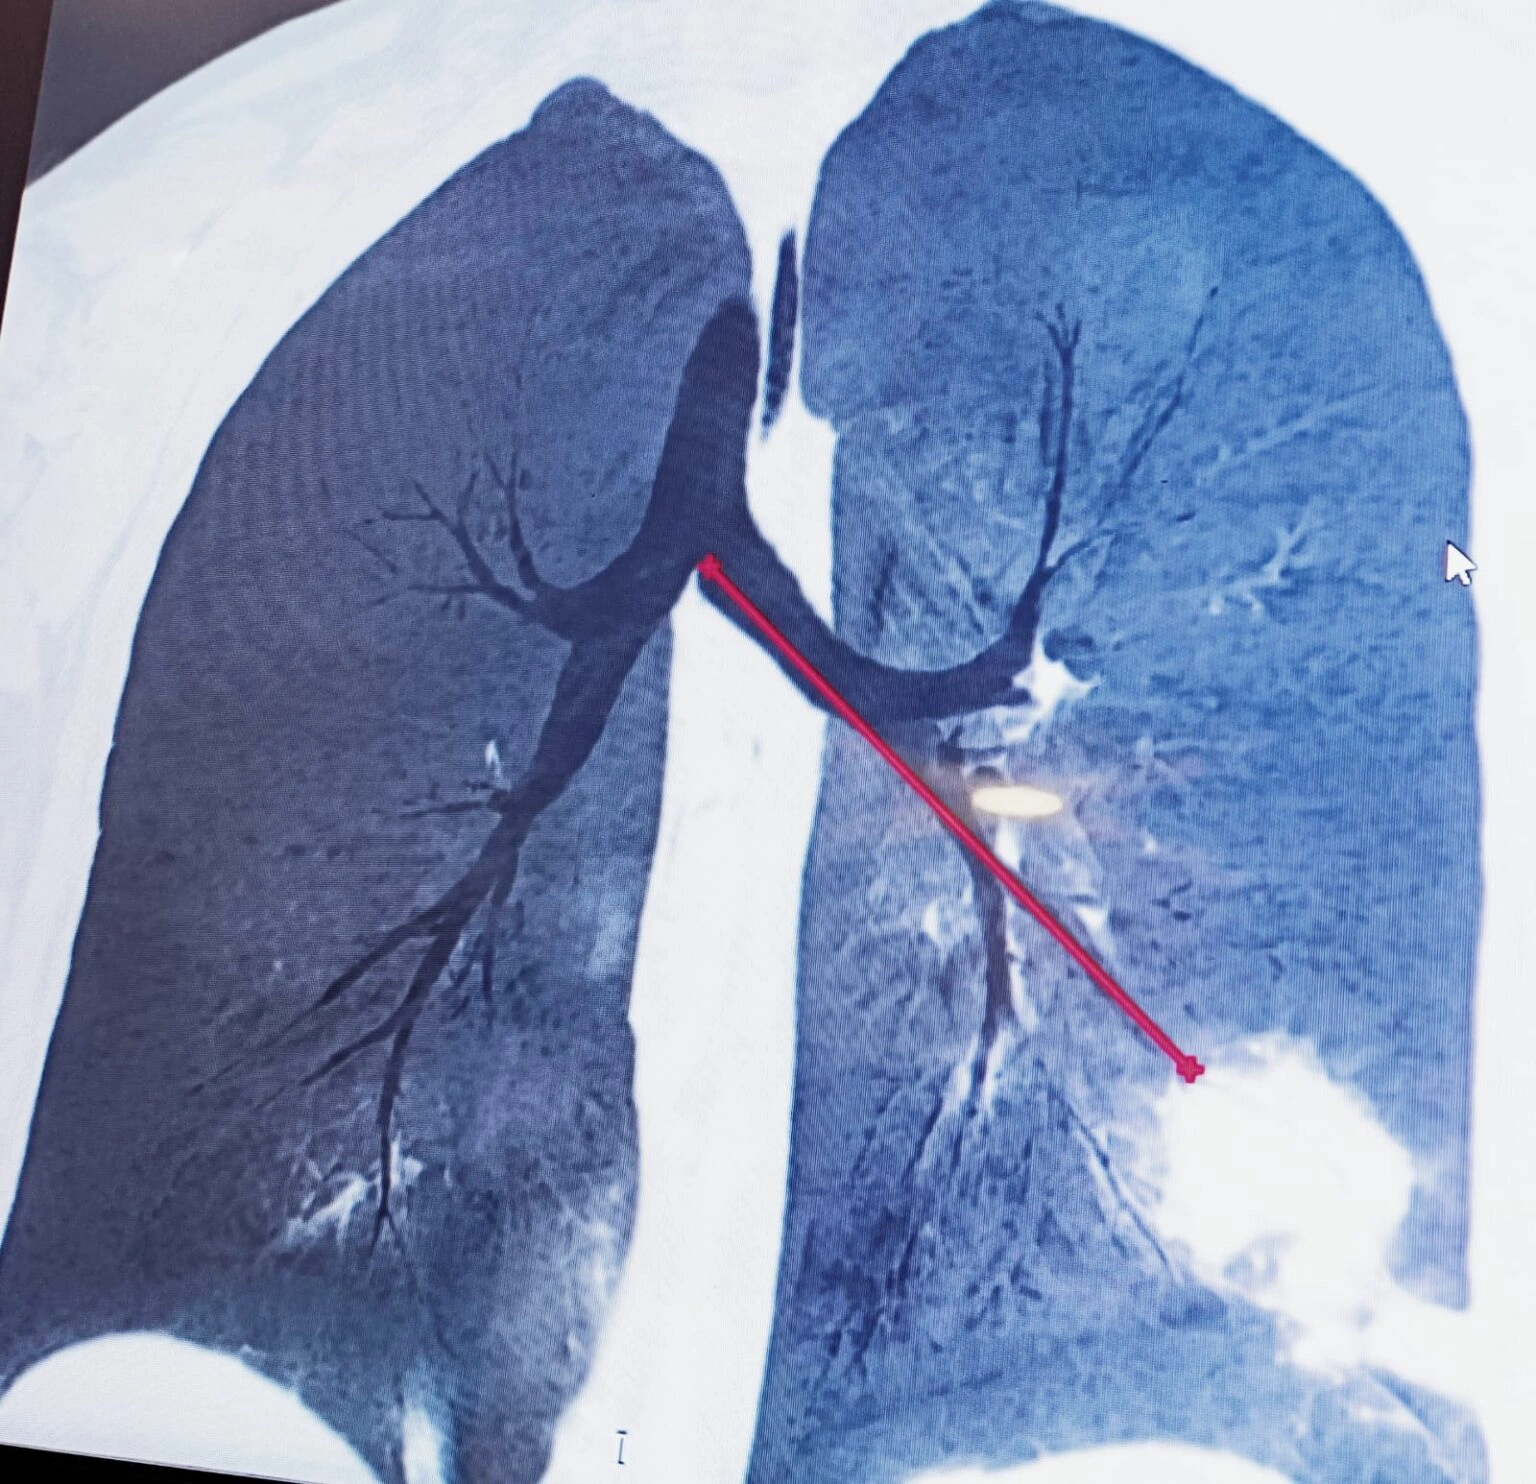

Transbronchial biopsy with Radial EBUS , Flouroscopic Guidance assisted by ROSE

Lesion in the lung biopsied with radial EBUS guidamce